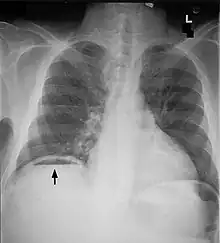

| Frontal chest X-ray. The air bubble below the right hemidiaphragm (on the left of the image) is a pneumoperitoneum. | |

When present, pneumoperitoneum can be seen on projectional radiography, but small amounts are often missed, and CT scan is nowadays regarded as a criterion standard in the assessment of a pneumoperitoneum.[18] CT can visualize quantities as small as 5 cm3 of air or gas.

Signs that can be seen on projectional radiography are shown below:

As differential diagnoses, a subphrenic abscess, bowel interposed between diaphragm and liver (Chilaiditi syndrome), and linear atelectasis at the base of the lungs can simulate free air under the diaphragm on a chest X-ray.